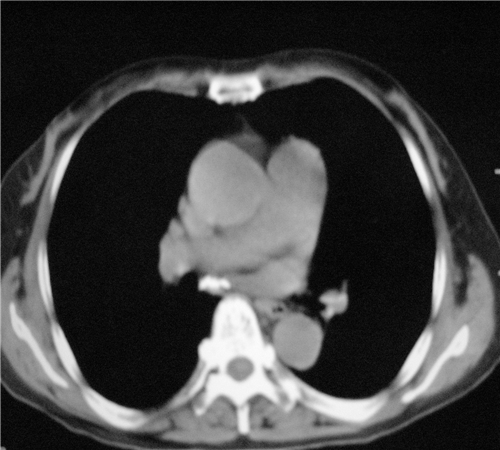

标题: CT26849:女67岁反复胸痛两天余,临床考虑夹层。 [打印本页]

标题: CT26849:女67岁反复胸痛两天余,临床考虑夹层。

右肺感染,未见夹层。

未见夹层

既然考虑夹层,建议强化!另:右下肺感染!

1)右肺感染性病变。2)建议行ct增强扫描或mri检查排除主动脉夹层。

双下肺感染,右侧显著。有无夹层,增强扫描后再诊断。

1. 感染性病变,2.未见夹层,3.食道未见异常。

平扫未见确切夹层征,建议必要时增强扫描或mri检查。